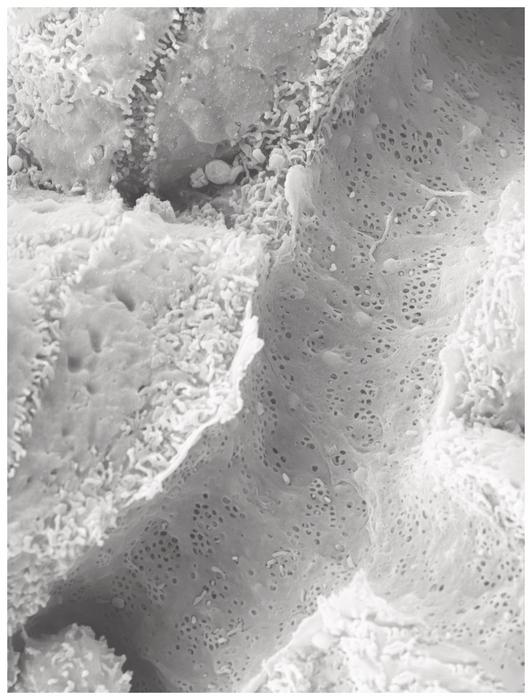

The leading role is played by windows (Latin: fenestrae) in the endothelial cells of blood vessel, through which substances are exchanged between liver cells and blood. The liver uses these tiny windows to release excess fat particles into the adipose tissue via the bloodstream. The researchers discovered that these windows are closed by a mechanism in which the signalling molecule SEMA3A (semaphorin-3A) plays the central part. This molecule is produced in blood vessels when they are overly exposed to the saturated fatty acid “palmitic acid“.

Sydney Balkenhol from the Institute of Metabolic Physiology at HHU and the DDZ, first author of the study now published in Nature Cardiovascular Research, points to a discovery made by the team using scanning electron microscopy: The “windows” in the smallest blood vessels of the liver were also closed in mice with fatty liver and type 2 diabetes mellitus.